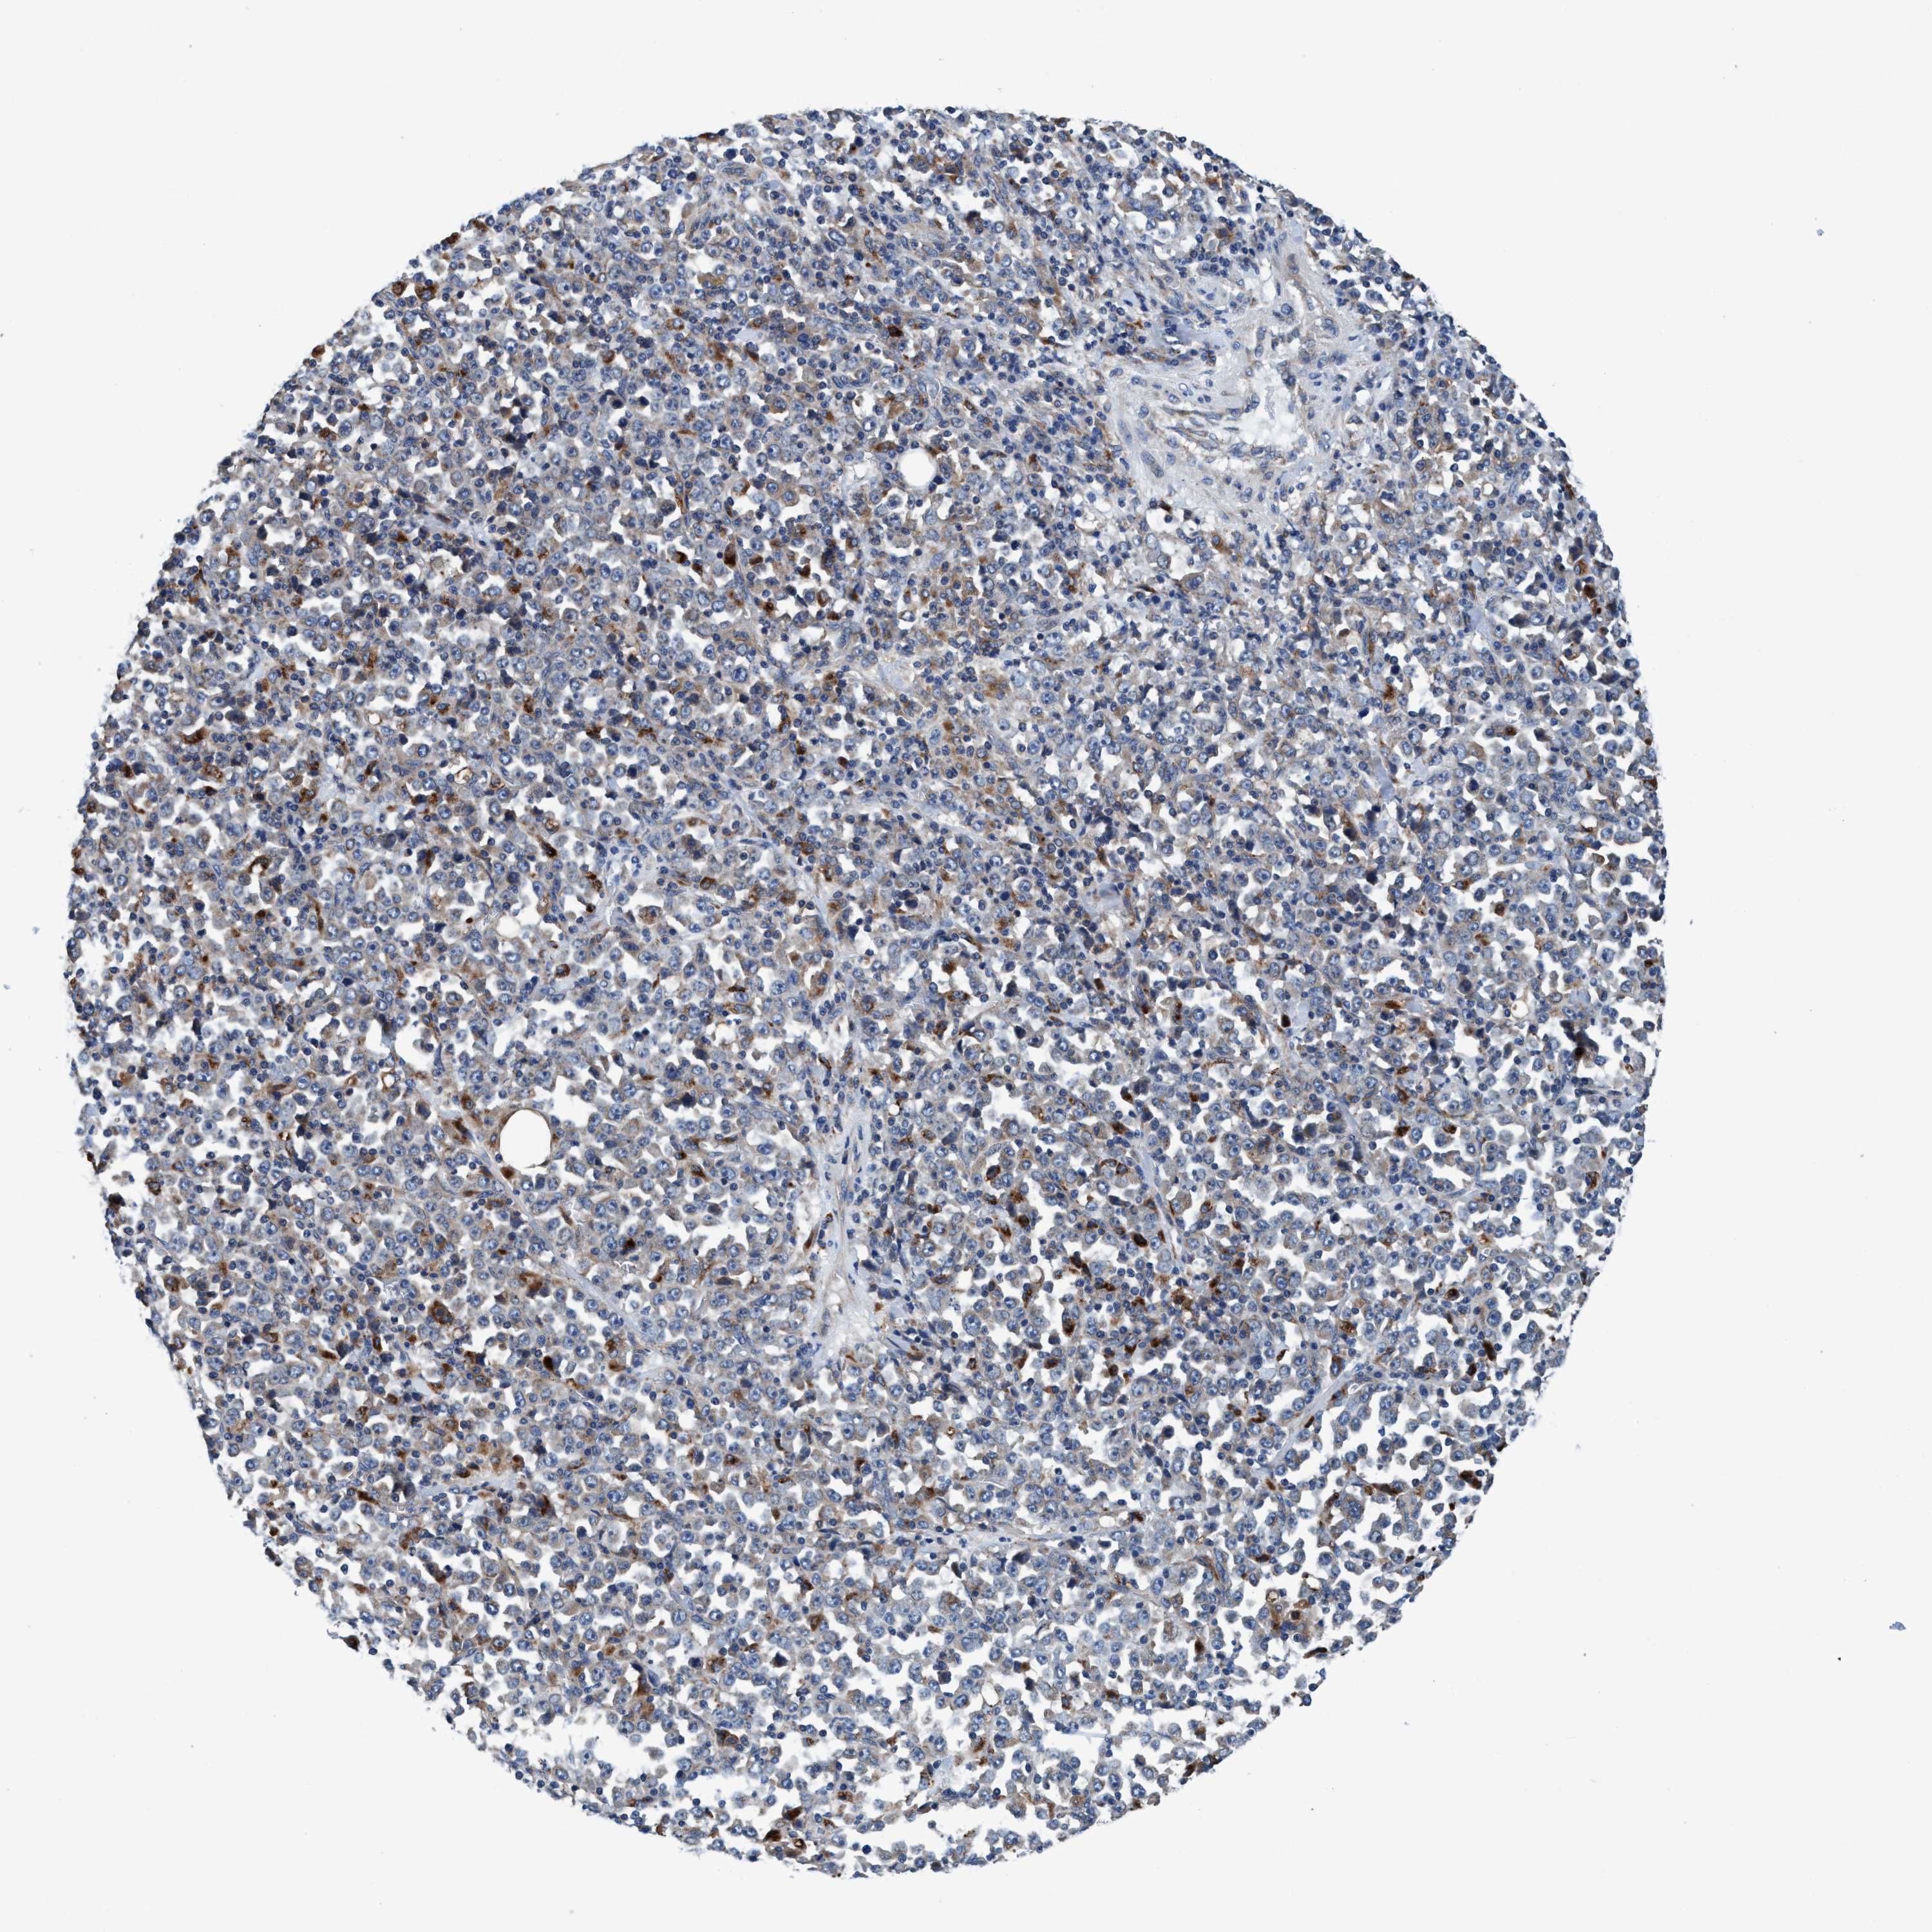

STOMACH CANCER - Protein expressioni

A mouse-over function shows sample information and annotation data. Click on an image to view it in a full screen mode. Samples can be filtered based on level of antibody staining by selecting one or several of the following categories: high, medium, low and not detected. The assay and annotation is described here.

Note that samples used for immunohistochemistry by the Human Protein Atlas do not correspond to samples in the TCGA dataset.

Antibody stainingi

Antibody staining in the annotated cell types in the current human tissue is reported as not detected, low, medium, or high, based on conventional immunohistochemistry profiling in selected tissues. This score is based on the combination of the staining intensity and fraction of stained cells.

Each image is clickable and will lead to virtual microscopy that enables deeper exploration of all samples and also displays staining intensity scores, fraction scores and subcellular localization as well as patient and tissue information for each sample.

Antibody HPA021335

Antibody HPA021830

Staining

High

Medium

Low

Not detected

Intensity

Strong

Moderate

Weak

Negative

Quantity

>75%

75%-25%

<25%

None

Location

Nuclear

Cytoplasmic/membranous

Cytoplasmic/membranous,nuclear

Adenocarcinoma, NOS